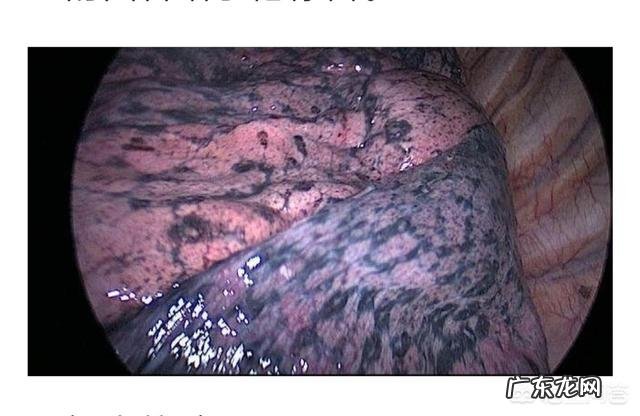

对于戒烟后出现的咳嗽,专家指出戒烟后的这种咳嗽是暂时性的,并不是疾病的表现,而是身体好转的迹象,属于好转反应的一种,也是肺部排毒的表现 。

医学专家研究发现,再戒烟以后短暂的时间内肺部就会发生变化:

戒烟一周后:肺部绒毛再生

戒烟一周后,肺部绒毛就会再生,肺部的纤毛是由过滤杂质和防止废物感染的作用 。吸烟者的支气管会在72小时之内放松,肺部呼吸能力相应增加 。